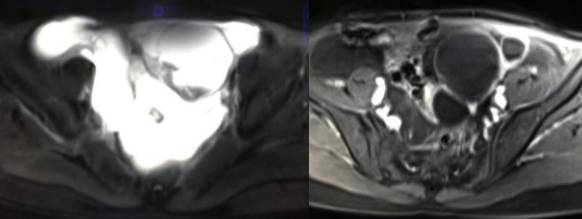

MR检查:

病理结果:黄体血肿

黄体血肿为正常排卵过程中,卵泡层破裂,引起出血,较多的血液潴留在卵泡或黄体腔内形成血肿。

正常黄体直径为15mm左右,以后转变为白体,并在下一个周期的卵泡期自然消退。若黄体内出血量较多,则形成黄体血肿,或称黄体内出血,出血性黄体。黄体血肿多为单侧,一般直径为40mm,偶可达100mm,黄体血肿被吸收后可导致黄体囊肿,较大的血肿破裂时可出现腹腔内出血,剧烈腹痛、少量阴道流血和腹膜刺激征,不易与宫外孕区别。

根据时间不同MR信号也有所不同,TIWI脂肪抑制序列能够鉴别脂肪和出血。